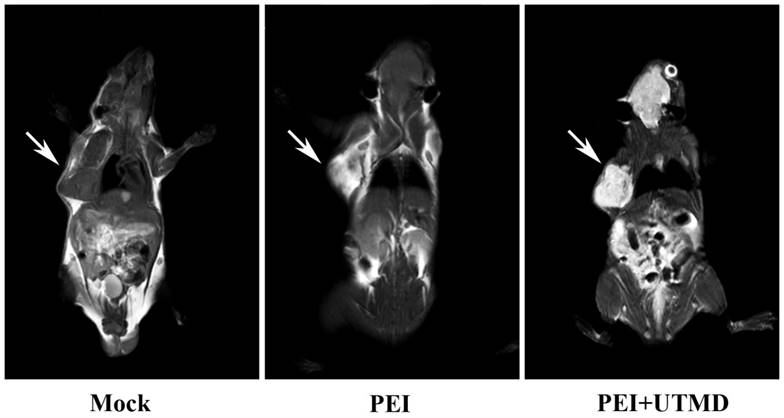

PEI nanohydrogel treatment combined with UTMD and MRI can support and improve the diagnosis and treatment visualization of pancreatic cancer in vivo

MRI scans of the nude mice (Fig. 6) showed higher signal in the tumors following injection with PEI nanohydrogel materials compared with before injection. This finding indicates that our prepared PEI nanohydrogels have the potential for tumor MRI as contrast agents in vivo. This signal was enhanced when UTMD was added.

Figure 6

Polyethyleneimine (PEI) nanohydrogels have the potential for tumor magnetic resonance imaging (MRI).

Additionally, this approach utilizes the multiple modification properties of nanohydrogels, including grafted Gd ions. This supports the use of tumor-targeted imaging with MRI and provides a new therapeutic visualization technology platform for pancreatic cancer chemotherapy.